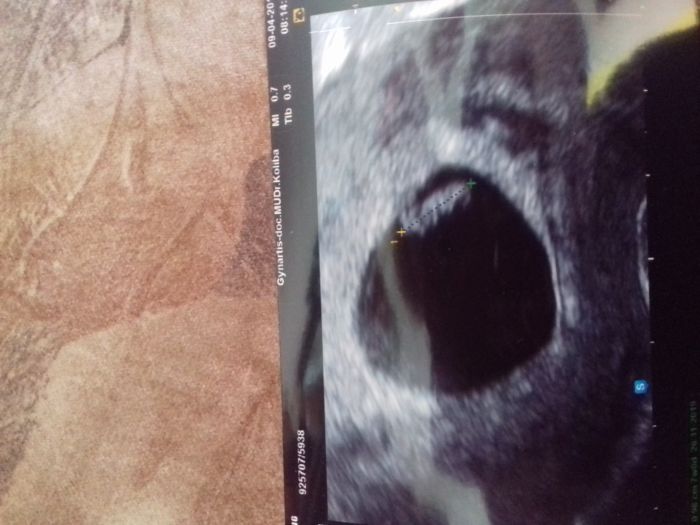

Holky,tak se hlasim po 1.ultrazvuku. Mimcu bine srdicko a ma skoro 7mm . Dle doktorky su 6+5 takze se termin porodu protahl az na 27.listopadu ,ale na ultrazvukove fotce je napsano 22.listopad - to podle me vygeneroval pc kdyz tam zadavala udaje o posledni menstruaci. Takze me jen zajima zda se mam ridit datem na fotecce nebo tim ze mi rekla ze teprv 6+5 cili porod az pozdeji, 27.11.2019 ? Asi to co rekla ze ? Jinak mi dala 3 fotky . No a trosku jsem byla zklamana,pac jsem tak moc doufala ve dvojcatka :D ale alespon to bude jednodussi pro me :D